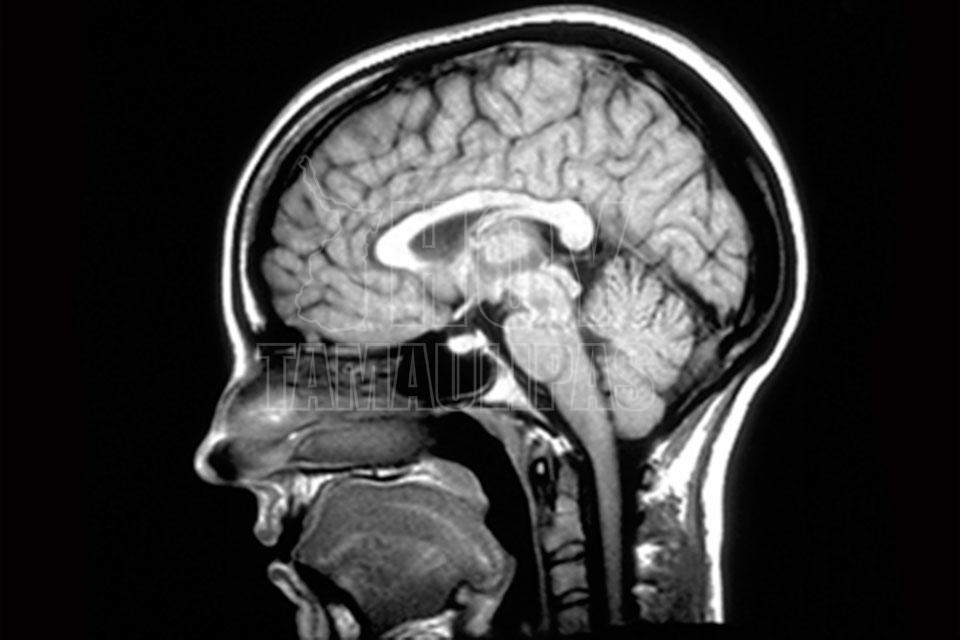

México, (Notimex).- Con apoyo de las universidades de Hannover, Alemania, y Libre de Bruselas, en Bélgica, un grupo de científicos, entre ellos el mexicano David Oliva, desarrolló un bisturí inteligente que facilitará la detección de tumores cerebrales.

A través de vibraciones microscópicas, esta tecnología detecta cuando un tejido cerebral es sano o fue afectado por un tumor, por lo que dará certeza y orientación a los neurocirujanos en su labor. De hecho, cuenta con sensores y algoritmos de procesamiento digital y emite señales de alerta que se podrán ver o escuchar.

El principio médico a partir del cual se trabajó en ese dispositivo es que un tejido sano tiene una forma de vibración diferente a una célula cancerígena.

Los científicos obtuvieron una fotografía de cómo el cerebro vibra y analizaron esas frecuencias para obtener un modelo matemático, lo que permitió identificar diferencias entre tejido sano y afectado en dicho órgano, diferencias que son imperceptibles para los cirujanos.